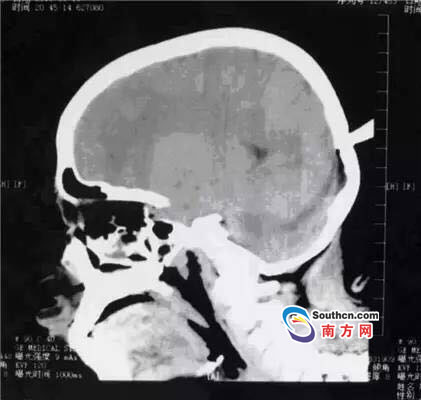

接到小玲受傷的消息,東莞市第三人民醫院急診科立即啟動了急癥危重患者搶救流程。急癥頭部CT顯示,飛鏢已穿透小玲的顱骨,并突破硬腦膜,情況非常兇險,小玲命懸一線。